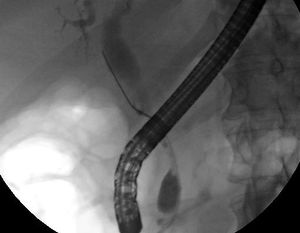

على الرغم من أن التصوير باستخدام الأشعة السينية غير الغازية في منطقة البطن يمكن أن يكون مفيداً في التشخيص، إلا أن التصوير الموضعي للقنوات الصفراوية غالباً ما يكون ضروريا. ومن بين أنواع الفحوص التي تستخدم على نطاق واسع في تشخيص أورام قنوات الصفراء تصوير البنكرياس بالتنظير الباطني بالطريق الراجع (ERCP بالإنجليزية) وهو إجراء من شأنه أن يجمع بين التنظير الخارجي والتنظير الداخلي ويقوم بهما طبيب الجهاز الهضمي أو الجراح. وعلى الرغم من أنها من الجراحات الغازية، ومحفوفة بالمخاطر أثناء وبعد العملية (زيادة التهاب البنكرياس في 5٪ من الحالات، فضلاً على الأخطار التقليدية للتنظير الداخلي)، إلا أنها تسمح بعمل مسح للخلايا بهدف بذل عينة أو وضع دعامة لأي تدخل جراحي آخر لتسليك انسداد قنوات الصفراء (توسع القنوات المرارية أو تحليل أي حصوات محتملة). ويمكن أيضا إجراء الكشف بالموجات فوق الصوتية بالمنظار في ذات الوقت[48].[49] · [50] · [51]. كما أن التصوير بالرنين المغناطيسي للبنكرياس والمرارة يعد تشخيصاً بديلاً غير غازي مقارنة بعملية التنظير الباطني بالطريق الراجع[49] · [50] · [51] . وقد اقترح بعض الباحثين أن يحل التصوير بالرنين المغناطيسي محل التنظير الباطني بالطريق الراجع في تشخيص سرطان القنوات المرارية[52] · [53] · [54] · [55] .